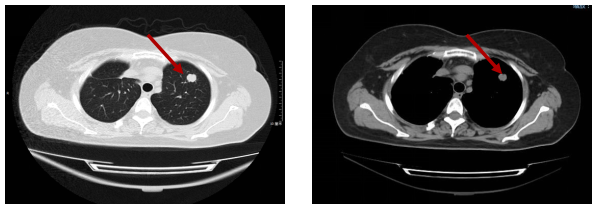

2016-11-10 复查胸部CT平扫示左肺新发结节,转移瘤可能大。2016-11 行左肺上叶结节楔形切除术。术后病理符合肠癌肺转移。术后继续卡培他滨维持治疗。(PFS 7个月)

图2 左肺新发结节(大小约1.2cm)